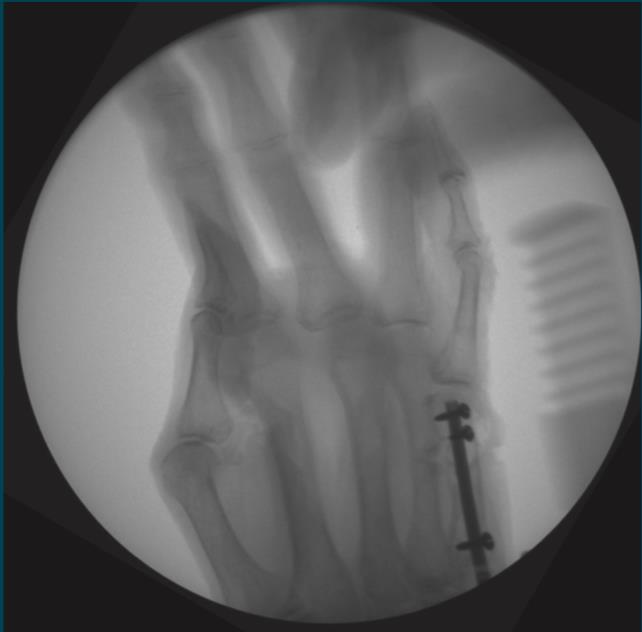

Locking Hand Nail System

• The Locking Hand Nail System from Skeletal Dynamics is an intramedullary fixation system designed for the stabilization of fractures of the metacarpals and proximal phalanges

• The device provides minimally invasive internal fixation through a headless, cannulated nail that is inserted within the medullary canal to maintain fracture alignment while minimizing soft-tissue disruption

• The system incorporates distal locking screw options to enhance rotational and axial stability, allowing controlled fixation of extra-articular fracture patterns

• The Locking Hand Nail System is part of a specialized hand fracture fixation platform and includes multiple nail diameters and lengths, dedicated instrumentation, and compatible locking screws to accommodate variations in hand anatomy and fracture configuration

• Metacarpal

• nails can be introduced either in an antegrade or retrograde direction

• the illustrated surgical technique uses an antegrade approach

• fully flex the metacarpophalangeal joint and mark the dorsal third of the metacarpal head

• open the 3rd extensor compartment for k-wire insertion into the metacarpal head

• Metacarpal Technique